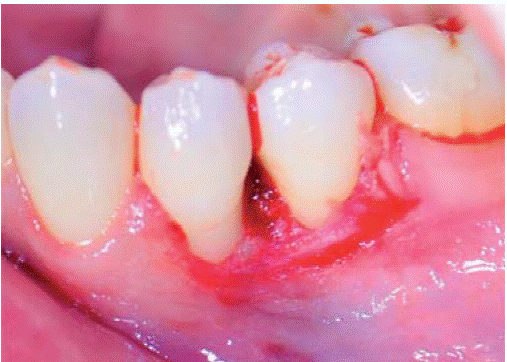

En la siguiente sesión se realizó la biopsia escisional de la lesión (Figura 4). En esta intervención se eliminó la lesión además de un margen de tejido sano llegando a remover el periostio adyacente. Se tomó la muestra para el examen histopatologico y fue transportado en formol al 10%. A continuación se realizó el recontorneado del tejido blando (gingivoplastia) (Figura 5) y se colocó un aposito de cemento periodontal. Se indicó analgésico por 48 horas y colutorios con clorhexidina al 0.12%, los cuales debieron ser suspendidos al quinto día debido a que la paciente presento lesiones del tipo ulcerativas a nivel de encía adherida por reacción alergica.

Tratamiento: primera sesión de instrucción de higiene oral seguido de biopsia excisional de lesión y gingivoplastia (Figuras 11 y 12).

Tratamiento: se realizó instrucción de higiene oral, raspaje y alisado radicular; seguido de la biopsia excisional de la lesión (Figura 19) y gingivoplastia. Además se indicó terapia periodontal de soporte con sesiones de mantenimiento periodontal cada tres meses durante el primer año.

Tratamiento: sesión de instrucción de higiene oral y biopsia excisional con gingivoplastia (Figura 23).